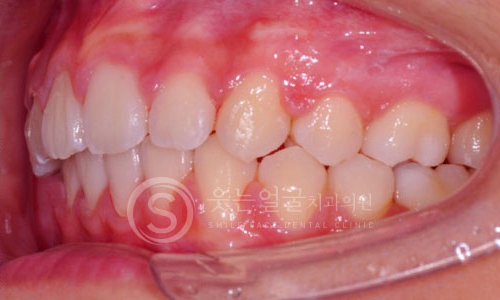

한눈에 보는

임플란트 전후사진

View more

환자 개개인의 치아 형태와 구강 구조에 맞춘 맞춤형 크라운

제작으로, 자연스러운 기능과 심미성을 동시에 제공합니다.